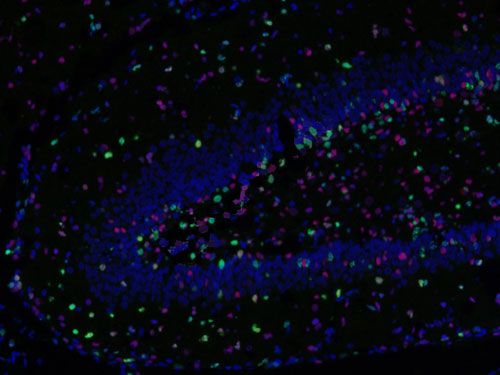

□免疫熒光多標陽性共定位分析:

測量整張掃描切片或者指定區域中單獨通道的數據以及指定共定位的數據(陽性面積或陽性率值表示,選其一)。

免疫熒光空間距離分析:

主要用來研究腫瘤微環境,炎性細胞和腫瘤細胞之間的距離關系等。

□分析一種指標標記的細胞周圍多少微米范圍之內另一指標標記的細胞數量,可以設置不同范圍;

□分析不同指標標記細胞之間的平均距離;

□以某處為界(如腫瘤灶、壞死灶或指定區域等)分析該區域多少微米范圍之內不同指標標記的細胞數量,例如腫瘤周圍500um內CD3陽性細胞的數量。

實驗結果展示: